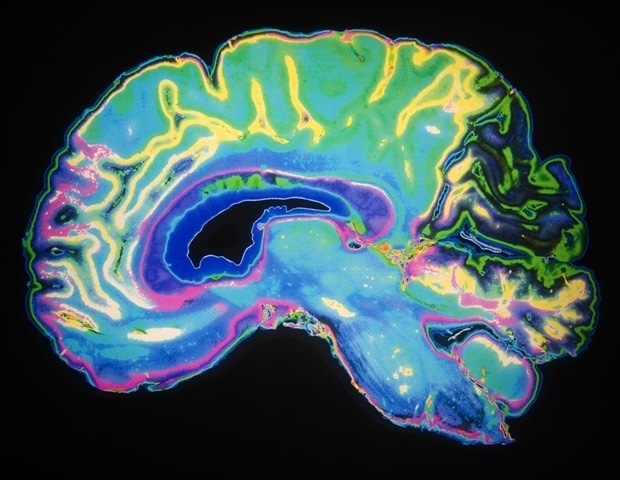

Πώς απομακρύνει ο εγκέφαλος τα απόβλητά του; Αυτή είναι η αποστολή του λεμφικού συστήματος του εγκεφάλου, και οι πρόσφατες προσπάθειες να κατανοηθεί η λειτουργία του έχουν επεκτείνει τα όρια των τεχνολογιών απεικόνισης του εγκεφάλου.

Μια νέα μελέτη που δημοσιεύθηκε στο περιοδικό iScience από ερευνητές του Ιατρικού Πανεπιστημίου της Νότιας Καρολίνας αποκαλύπτει, για πρώτη φορά σε ανθρώπους, την ύπαρξη ενός άγνωστου κόμβου στο λεμφικό σύστημα του εγκεφάλου – την μέση μηνιγγική αρτηρία (MMA). Η ερευνητική ομάδα, υπό την καθοδήγηση του Δρ. Όντερ Αλμπαγιράμ, χρησιμοποίησε τεχνολογία MRI σε πραγματικό χρόνο, που αναπτύχθηκε αρχικά για να μελετήσει πώς η διαστημική πτήση επηρεάζει τη ροή των υγρών στον ανθρώπινο εγκέφαλο, σε πέντε υγιείς συμμετέχοντες κατά τη διάρκεια έξι ωρών.